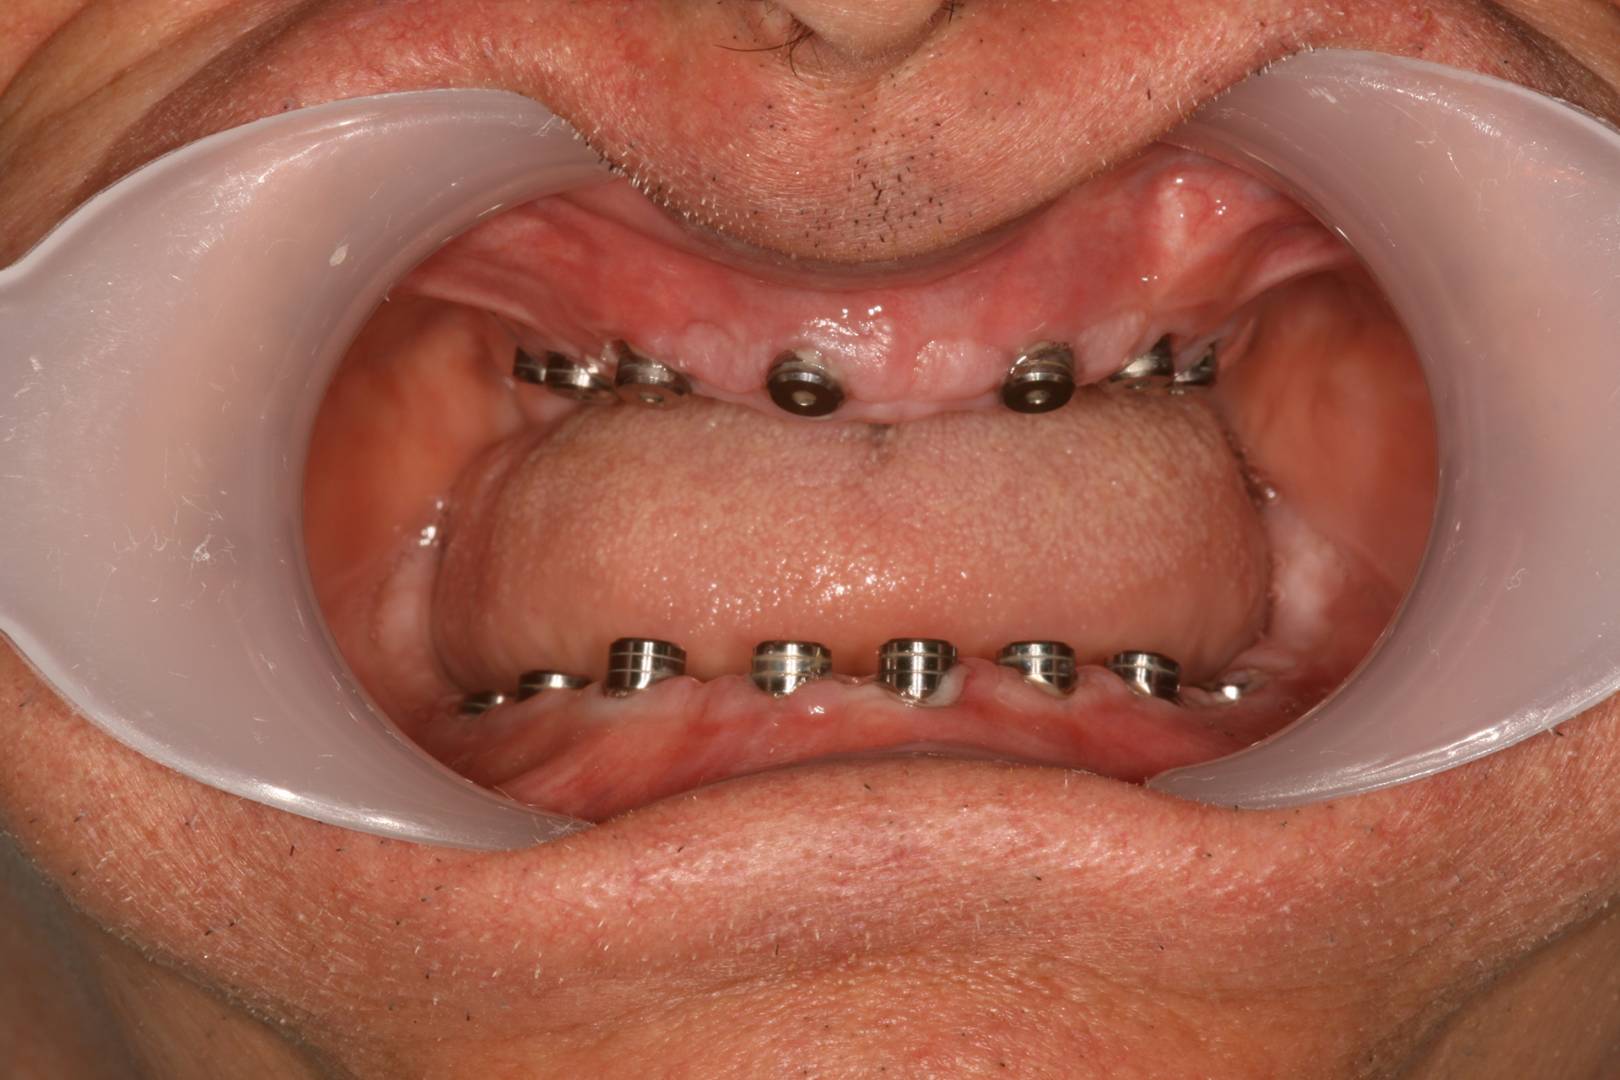

Implantátumok előtte-utána

Fogászati implantátumok előtte-utána

Implantátum beültetés előtt és után